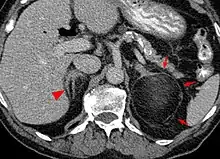

| An adrenal myelolipoma | |

Myelolipomas can present in the adrenal gland,[2] or outside of the gland.[3]

Most myelolipomas are unexpected findings on CT scans and MRI scans of the abdomen. They may sometimes be seen on a plain X-ray films.[4]